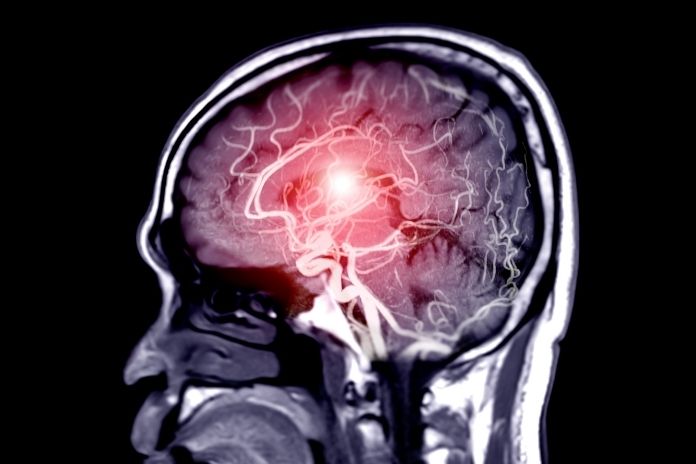

If your headache pattern keeps changing, or if it’s your first-ever exertion headache, then visit a neurologist. Imaging (MRI, CTA, or MRA) aids in detecting/ruling out aneurysms, bleeding, or structural problems.

A neurological examination tests vision, reflexes, and coordination. MRI or MRA scans are used to eliminate secondary causes like bleeding or aneurysm if red flags are present.